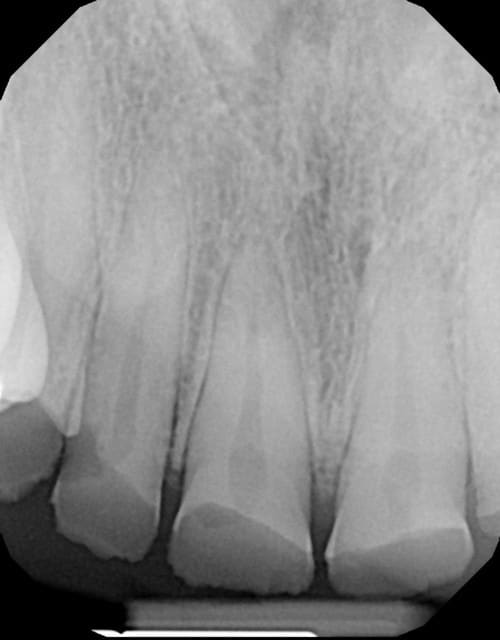

> Femme de 39 ans

> Histoire médicale RAS

> Pas de douleur (ATM, muscles, dents RAS)

> Demande solution globale/esthétique.

>

> La 21 mesure 8,6 mm par 3,6 mm de haut...

> hummm je crois qu'il y a usure...

> Alors des solutions ?

cas classique d'abrasion avec compensation au niveau des procès alvéolaires donc pas de perte de DV donc pas de surélévation

au niveau antérieur suivre ls principes de Peter Dawson

au niveau postérieur, coronoplasties , élongations coronaires pour recréer un plan occlusal correct,

après implants ou partiel

une certitude pas de pb paro sinon il ya longtemps que les dents antérieures auraient disparues ...